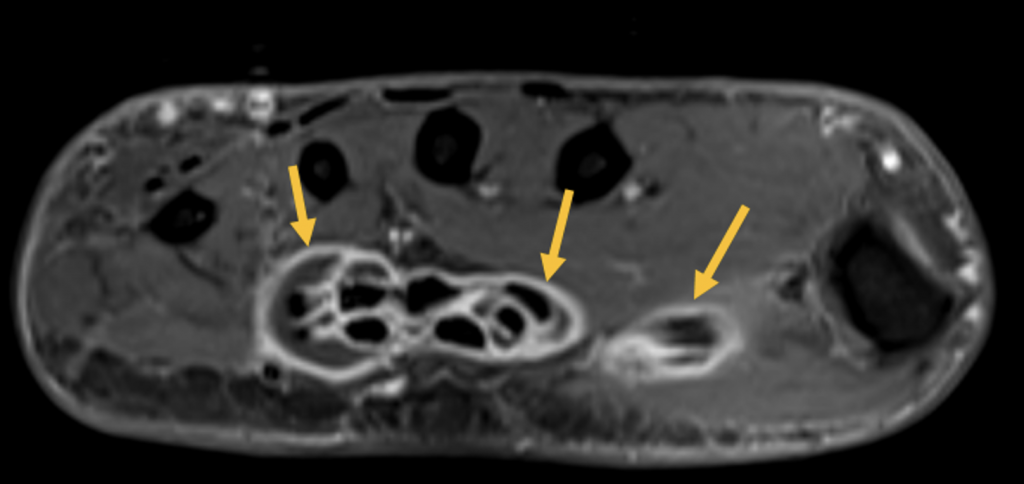

- Ausgeprägte Tenosynovitiden, v.a. der Flexorensehnen (Pfeile) (T1 FS KM)

- Diffuses Weichteilödem entlang des 5. Strahles mit korrespondierender KM- Aufnahme (Pfeile) (T1 FS KM)

- Zusätzliche diffuse ödematöse Veränderungen im Subkutangewebe der gesamten Hand (Pfeile) mit fehlender oder nur sehr wenig korrespondierender KM Aufnahme